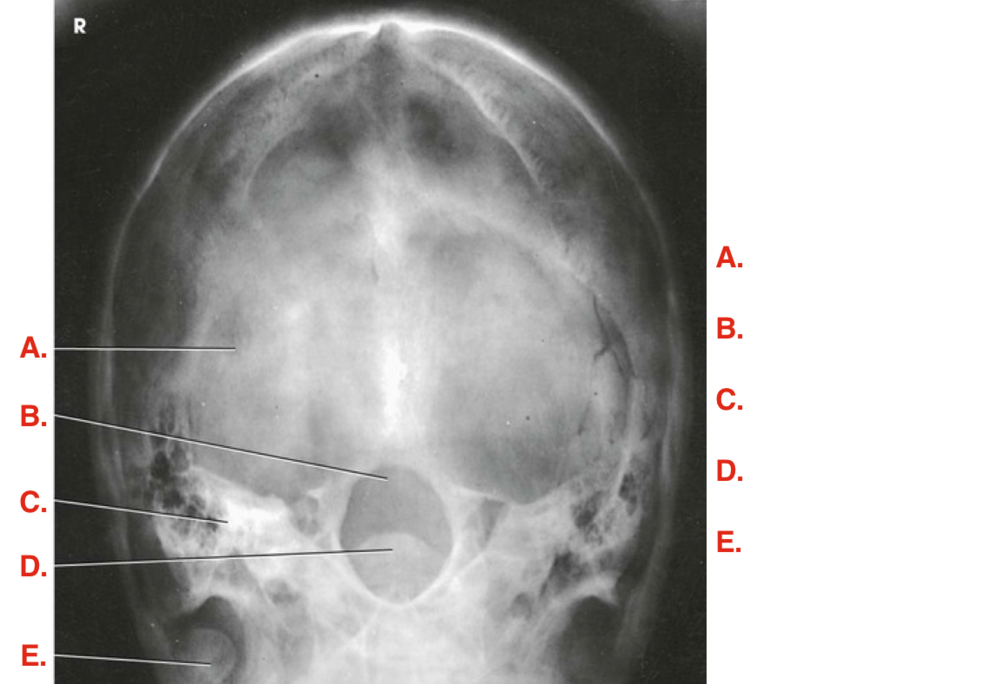

Label the image

Answer

supraorbital margin

sella turcica

external acoustic meatus

temporomandibular joint

petrous portion